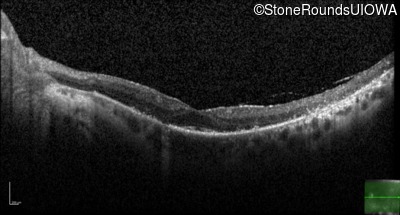

Optical Coherence Tomography - Left - 20/25 sc

Exemplar / OCT Stack